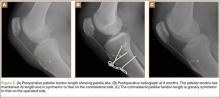

Because all cultures were negative, all laboratory examinations did not indicate any residual infections, and no bony involvement was noticed intraoperatively or in the preoperative knee MRI, we decided to proceed with the second stage of the Masquelet technique after 2 weeks. The patient returned to the operating room for final reconstruction of his patellar tendon using a custom-ordered cadaveric tendon–patellar tendon–bone allograft, the length of which was determined by measuring the contralateral patellar tendon, ie, 5.18 cm (Figure 1A). The previous anterior knee incision was reopened and extended distally past the tibial tuberosity and proximally toward the quadriceps tendon. The antibiotic spacer was removed. We proceeded with a repeat irrigation and débridement and the allograft transfer. The selected allograft was customized by reducing the tibial bone component to an approximately 1×2-cm bone block and by reducing the allograft patellar thickness with an oscillating saw, leaving an approximately 2-mm thick patellar bone graft attached to the patellar tendon. In a similar technique using an oscillating saw, we shaved off the anterior cortex of the patient’s patella to accommodate, in a sandwich fashion, the patellar allograft. Proximally, the quadriceps tendon insertion was split longitudinally and partially separated from the superior pole of the patellar tendon to allow seating and fixation of the modified quadriceps allograft tendon component.

We proceeded with the fixation of the allograft first distally on the patella. The anterior cortex of the tibial tuberosity was resected to allow the perfect seating of the bone block allograft. The graft was secured with a 4.0-mm fully threaded cancellous lag screw and reinforced with a 2.4-mm, 3-hole T-volar buttress plate (Synthes, Paoli, Pennsylvania). The plate was contoured to better fit the patient’s tibia. We sutured the patellar allograft tendon to the patella using two No. 2-0 FiberWire sutures in Krackow suture technique8 (Figures 1B, 1C). We obtained good fixation of the patellar tendon, and the distance between the patellar insertion and the inferior patellar pole was the same as before surgery: 5.57 cm and comparable to the contralateral side (Figures 2A-2C). The patellar allograft and autograft sandwich were secured with additional No. 2-0 FiberWire sutures, and the quadriceps allograft and autograft were secured with the cross-stitch technique with the same material. Fine suturing of the quadriceps tendon was done with No. 0 Vicryl sutures. After the fixation was completed, we tested the stability of the reconstruction and found good flexion up to 120°.

The patient was seen in clinic 3 and 9 months after surgery. At the 3-month follow-up appointment, the patient’s examination showed knee ROM from 0° extension to 130° of flexion, no secondary infection signs, and radiographic evidence of a well-healing patellar allograft with symmetric patellar tendon length to the contralateral side. At 9-month follow-up, the patient’s active ROM was from 0° extension to 140° flexion (Figures 3A, 3B), and he had returned to his preinjury level of functioning.